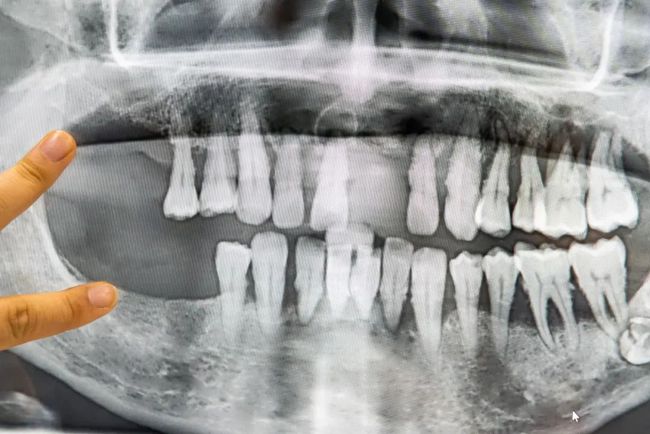

医生还为我们介绍了种植的适用范围

单颗牙缺失、多颗牙缺失、

半口缺失、全口缺失等

无论什么年龄段,

在海德堡口腔都拥有多个成功案例。

医生介绍,

如果自然牙的最大咀嚼力是100的话,

那么假牙的咀嚼力是15~20,

而人工种植牙能发挥到80~90的力度。

同时,

种牙可以让牙槽骨及牙龈快速恢复,

还可为进食提供保障。